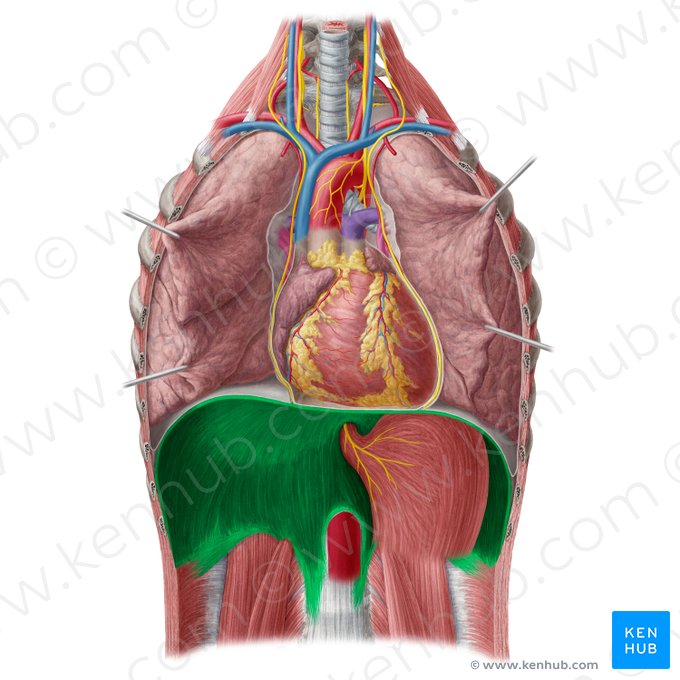

Diaphragma

Inandning